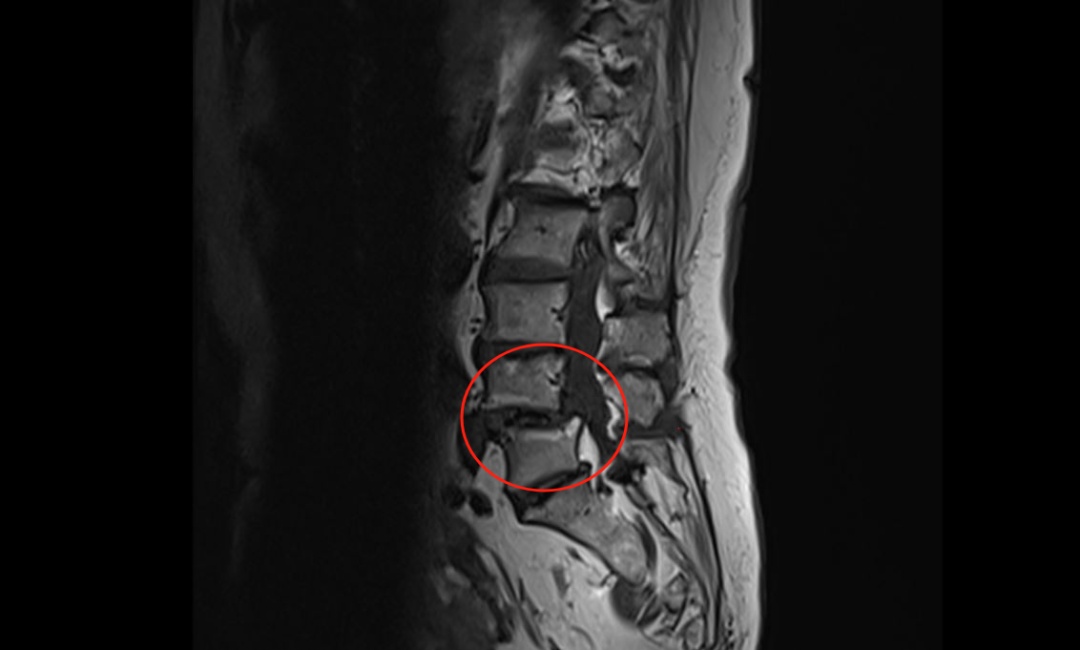

腰椎MRI提示腰椎滑脱